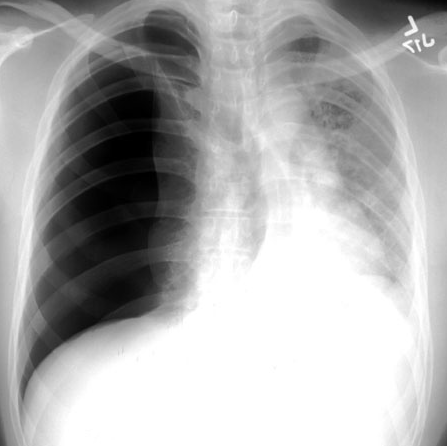

A patient reports to the ER following an accident while playing football. Paramedics on the scene report an onset of tachypnea and a CXR is taken. What is the diagnosis?

The chest radiograph shows hyperlucency on the right. This is consistent with a pneumothorax.